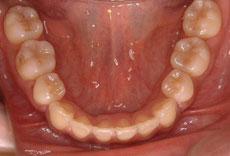

Y.K様 デイモンシステム

30代 女性 会社員

症例: 施術前・施術後

装置 | デイモンシステムクリア |

治療方法 | 下顎の左右の第一小臼歯と左下の第一大臼歯を抜歯しました。 |

治療前の状態 | 治療の経緯はわかりませんが、小学校の時に上顎の左右の犬歯を抜歯しています。 抜歯して部分的に矯正治療を行ったとの事でした。 それもあり、上下のバランスが悪く全体的にあまり咬んでいない状態でした。 また、左下の第一大臼歯の状態が悪く、抜歯しなければならないと一般歯科の先生よりアナウンスがあったとの事でした。 |

治療 | 上顎はすでに左右の犬歯が抜歯されているので、これ以上の抜歯はおこなえません。 下顎は上顎に対し全体的に前方にでていることもあり、左右の第一小臼歯を抜歯することになりました。また、左下の第一大臼歯の状態が悪かったため、その歯を抜歯し、その奥の第二大臼歯を第一大臼歯の代わりにするように前方に移動させ、その奥にある第三大臼歯(親知らず)を第二大臼歯の代わりになるように移動させるプランになりました。 その際、第一大臼歯を抜いた大きなスペース分を第二大臼歯を前方へ移動させる事は非常に困難で、前方の歯を固定し、引っ張れば善歩の歯が影響を受けて奥に引っ込み過ぎてしまう事が想像されます。 そこで、歯を抜いた第一大臼歯付近に矯正用のインプラントを軸として埋入し、動かない固定源を作り、そこから第二大臼歯と第三大臼歯を後方へ移動させました。 |

結果 | 全体のデコボコが治り、下の前歯の前突感も解消され、咬み合わせも良好な状態となりました。 また、左下の部分も奥歯2本をうまく前方移動できています。 一般的には奥歯二本を前方に移動する事は極めて困難な為、抜歯した第一大臼歯の部分には、インプラントやブリッジといった手法で人工物が入る事が多いですが、矯正用のインプラントを使用する事で、それを回避する事ができた症例です。 患者様にとっては非常にメリットがあったのではないかと思います。 |